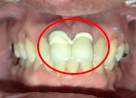

ブリッジの支台になっている前方の歯が、歯根の破折を起こしていました。真っ二つに割れていましたので、保存することができず抜歯しました。抜歯後2本欠損のところに、2本インプラントを埋入しました。

所感

抜歯後、ブリッジ、部分入れ歯の選択肢もありましたが、「自分の歯と同じように食事ができるインプラントでお願いします。」とおっしゃられました。咬合力がとても強い方でしたので、もし再度ブリッジにしていたら再度歯根の破折を引き起こし、さらに歯を失っていた可能性が高い方でした。インプラントは、それ自身が単体で植立し、単独で咬合力を負担します。ブリッジや部分入れ歯のように他の歯に負担を負わせることがないので、他の歯を守ります。インプラントにして正解だと考えます。今回もX-Guideを使った埋入で、安心安全に行うことができました。

Before

歯根が真っ二つに割れていました

抜いた歯

【抜歯後】

After